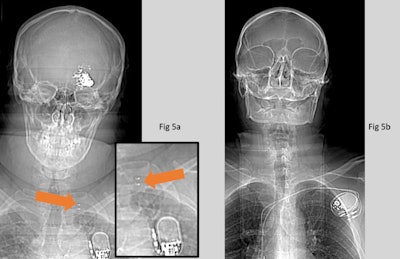

Both readers failed to identify two neurovascular stents, two coronary stents, and one of the three carotid stents (see figure below).

Additionally, reader one missed an iliac stent and a breast clip. But from the list of implants included in this work, all high-risk implants that have led to documented injuries or death following MRI, such as aneurysm clips and active implants, were identified. All active implants were recognized as such. But in some cases, they were incorrectly identified (e.g., pacemaker instead of VNS, as shown in the first figure).